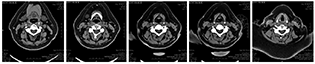

电子喉镜检查:位于"会厌结节下凹陷"上方[2],会厌喉面中央偏右,可见菜花样广基新生物,约1.0 cm×1.0 cm×0.5 cm,质脆,部分覆白色苔膜,边界不清,肿瘤未侵及双侧室带及前连合(图1)。病理检查提示为:中分化鳞状细胞癌;颈部淋巴结彩超检查:双侧颈部淋巴结可见,淋巴门清晰,未见明显异常淋巴结;喉部CT:会厌结节偏右局部增厚,密度增高,未见异常淋巴结及会厌前间隙受侵及征象(图2)。术前血常规、凝血项及生化全项等常规检查未见异常;肝胆脾超声及肺部CT未见异常。

患者电子喉镜显示会厌喉面广基新生物,病理检查为中分化鳞状细胞癌,喉部CT提示会厌结节偏右局部增厚,密度增高,未见会厌前间隙及喉外侵及,颈部淋巴结彩超提示未见异常淋巴结,全身检查未见明显异常。故诊断为:声门上型喉癌(T1N0M0)。